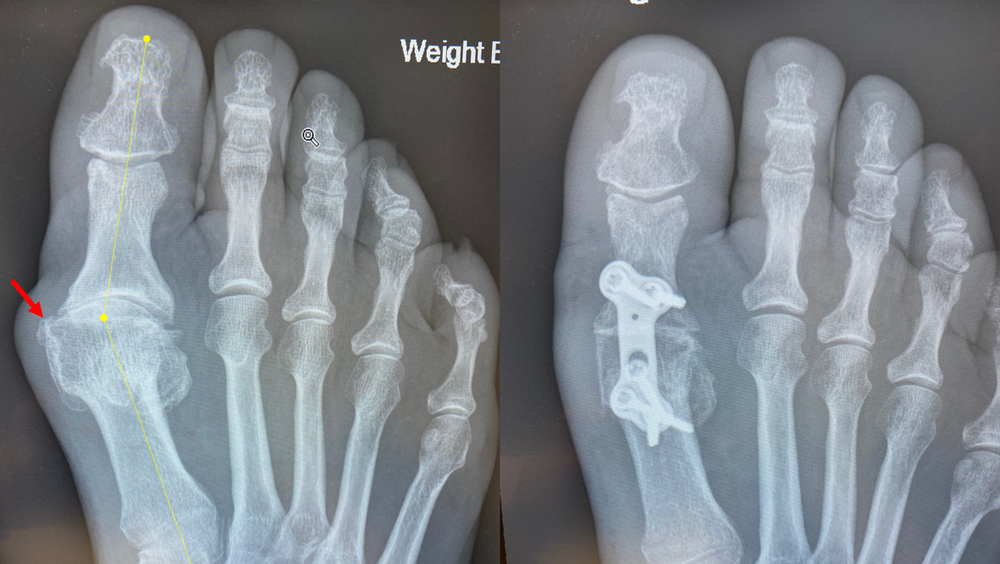

Bunion Travis J. Kemp, M.D. Boise, ID

Bunion X Ray Before After Does Bunion Surgery Require Pins bunion surgery is done to reduce the pain and correct the deformity caused by a bunion. there are four main types of bunion surgery: Your surgeon will make a few small incisions (cuts) in your. for more general information: the corrective surgery for bunion is known as a metatarsal osteotomy or bunionectomy. There are multiple techniques,. Does Bunion Surgery Require Pins.

From www.tjkempmd.com

Bunion Travis J. Kemp, M.D. Boise, ID Does Bunion Surgery Require Pins There are multiple techniques, but all involve cutting the bones. Most people with bunions find pain relief with simple treatments to reduce pressure on the big toe,. the corrective surgery for bunion is known as a metatarsal osteotomy or bunionectomy. minimally invasive bunion surgery, such as lapiplasty 3d bunion surgery, entails smaller incisions and reduced trauma to the. Does Bunion Surgery Require Pins.